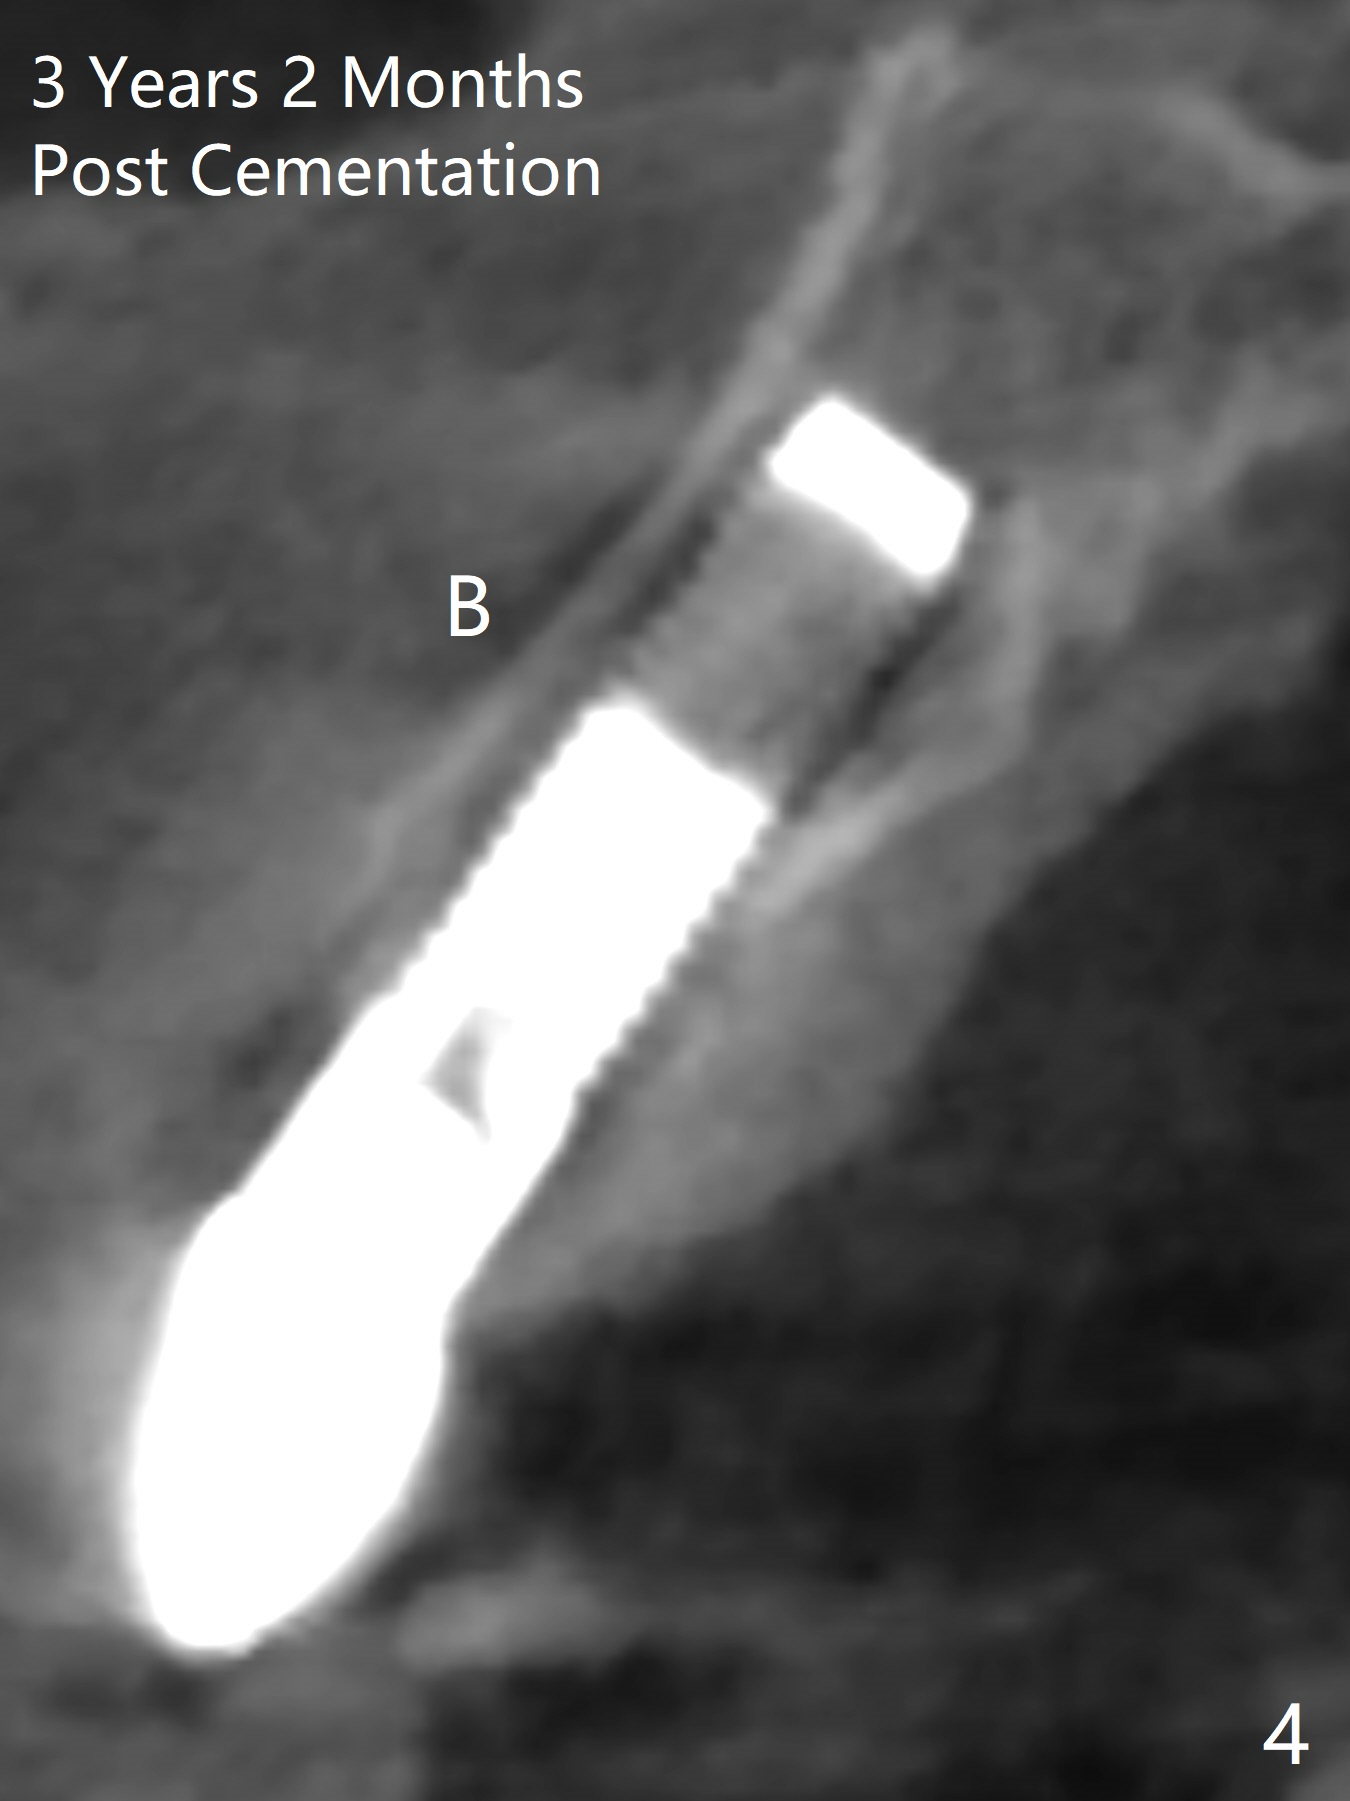

A 61-year-old man has chronic periodontitis and bruxism (Fig.1). Immediately after extraction and Clindamycin socket treatment, osteotomy is initiated with a 2 mm pilot drill at 20 mm in the lower 1/3 of palatal wall with normal saline irrigation, followed by 2.5-4 mm reamers at 20 mm (bone saved, Type III bone). A screw Implant (4.5x20 mm) is placed (45-50 Ncm, Fig.2). The root measurements were B-L 6.5 mm and M-D 5 mm. Autogenous bone is mixed SynthoGraft (size 50-500) ~ .3 g and blood. A 3.5x5 mm abutment is immediately cemented with an immediate provisional. There is positive bone growth 3 years post cementation (Fig.3 *). There is no buccal plate bone resorption 3 years 2 months post cementation (Fig.4 CT).